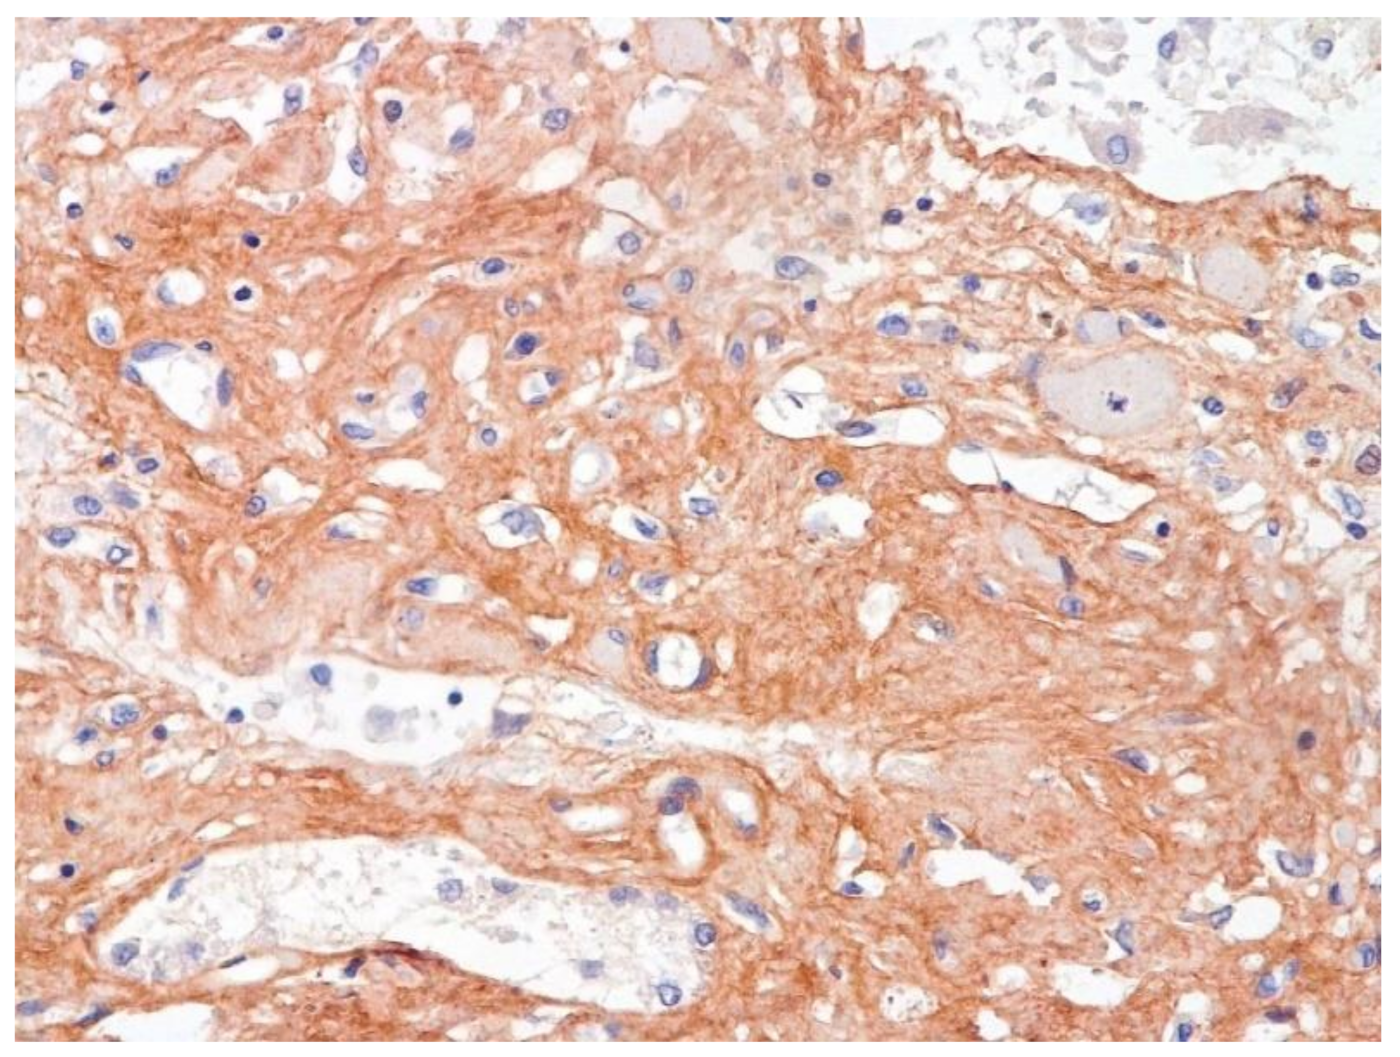

We consider certain changes to be directly related to virus propagation. We succeeded in detecting virus spike antigen in the bronchiolar epithelium (Figure 1) and macrophages (Figure 2) as well.

The dynamics of changes in ARDS associated with COVID-19 can only be judged by analogy with SARS and influenza A/H1N1pdm. In the late (productive) stage (after 7–8 days or more from the onset of the disease) of diffuse alveolar damage, macroscopically the lungs are enlarged, low-air, dense, fleshy, and can resemble the density of the liver, sometimes with diffuse whitish layers and areas of different sizes. Microscopically, siderophages, a relatively (in comparison with swine influenza) small number of hyaline membranes (Figure 9), fibrin, squamous metaplasia of the bronchial, and bronchiolar and alveolar epithelium can be detected in the lumens of the alveoli, respiratory and terminal bronchioles, the thickening of the interalveolar septa due to sclerosis, lymphoid (mostly CD3+ and CD 8+) (Figure 10 and Figure 11) and macrophage (Figure 12) infiltration, and the proliferation of type II alveolocytes. The nature of cytoproliferative changes of the epithelium in the trachea and bronchi remains unclear. In the final stage of the disease, sections of fibrous tissue may develop in all parts of the lungs (usually in the lower lobes) (Figure 13), which contributes to the development of chronic respiratory failure. It is notable that near the overgrowth of collagen fibers in the lungs, neoangiogenesis is also typical (Figure 14). The electron microscopic study revealed changed viral particles (Figure 15).

Figure 13. Fibrosis in lung due to collagen 3. IHC ×200.